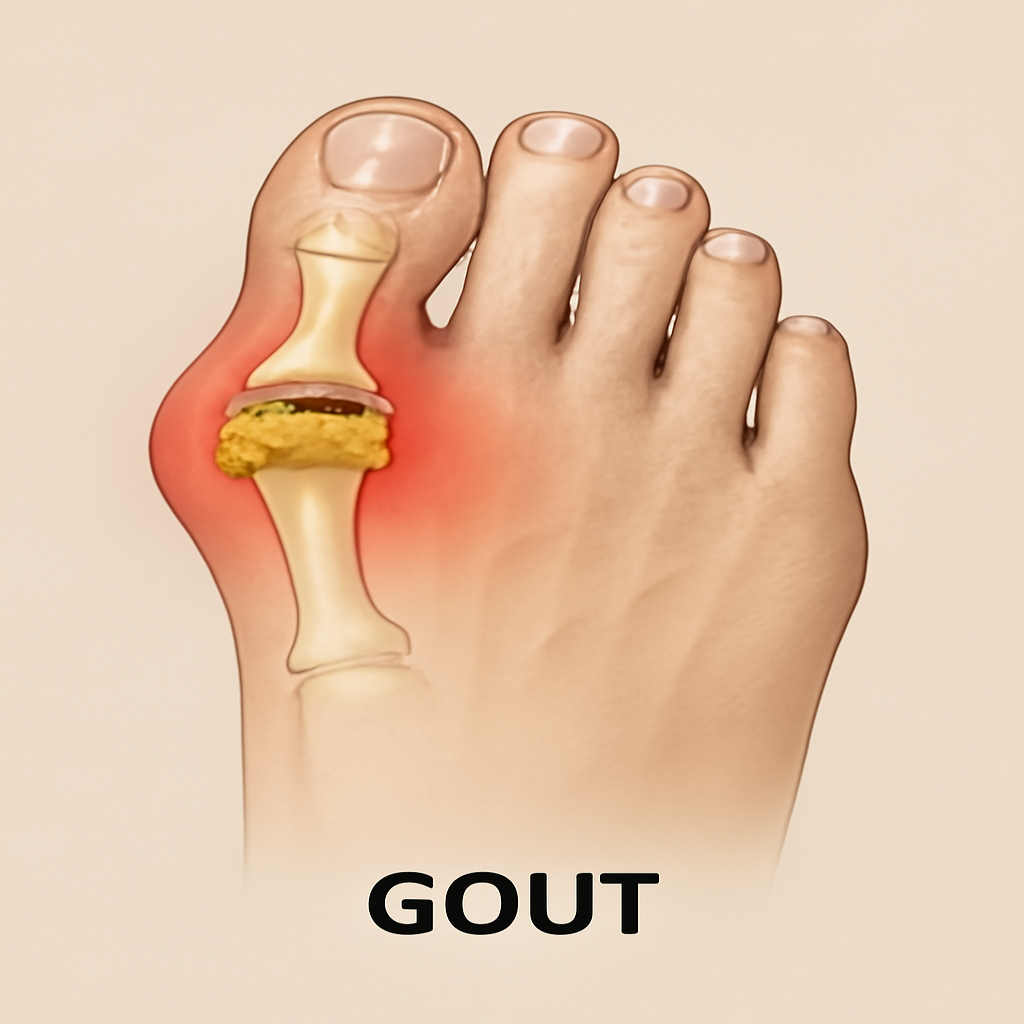

# Bones & Joint